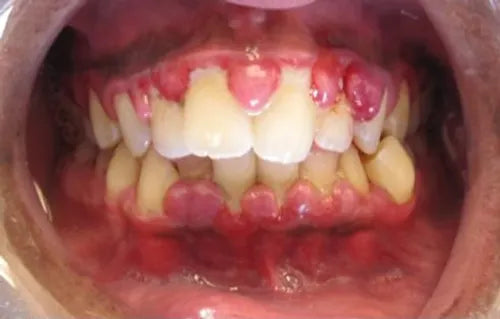

Gingivitis is the earliest stage of gum disease (also known as periodontal disease). It’s marked by inflammation of the gums, typically caused by the buildup of plaque along the gumline. Left untreated, gingivitis can evolve into more serious conditions like periodontitis, where the gums pull away from the teeth and even bone loss can occur.

Common symptoms of gingivitis include:

Red, swollen gums

Bleeding when brushing or flossing

Tender or sensitive gum tissue